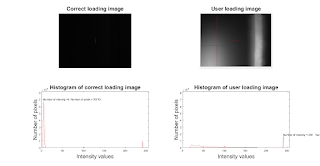

% read a CT image I=imread('./Abdominal wall normal anat (8).png');

plot histogram of the image

subplot(311); % plot to ensure a correct image is loaded.

imhist(I)

subplot(3,1,2:3);

imshow(I);

colorbar